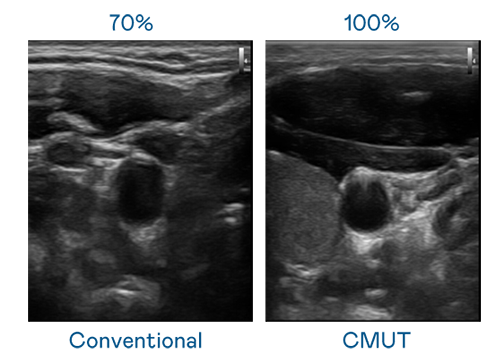

CMUT 技術是一種用電容式微機電元件來產生超音波訊號的技術。與傳統 PZT 壓電式技術相比,CMUT 頻寬增加 30%,更寬頻的超音波訊號讓影像解析度大幅提升,是實現高影像品質醫療超音波掃描、促進精準醫療發展的關鍵技術。

大頻寬帶來超清晰影像

超音波影像的解析度高低,首先取決於探頭能發出的訊號頻寬。304永利集团 CMUT 可提供高清晰的超音波訊號,提供高頻寬、高靈敏度、影像紋理細節更高的超音波影像,協助醫護人員縮短影像判讀時間及利用精準的醫療影像進行診斷。